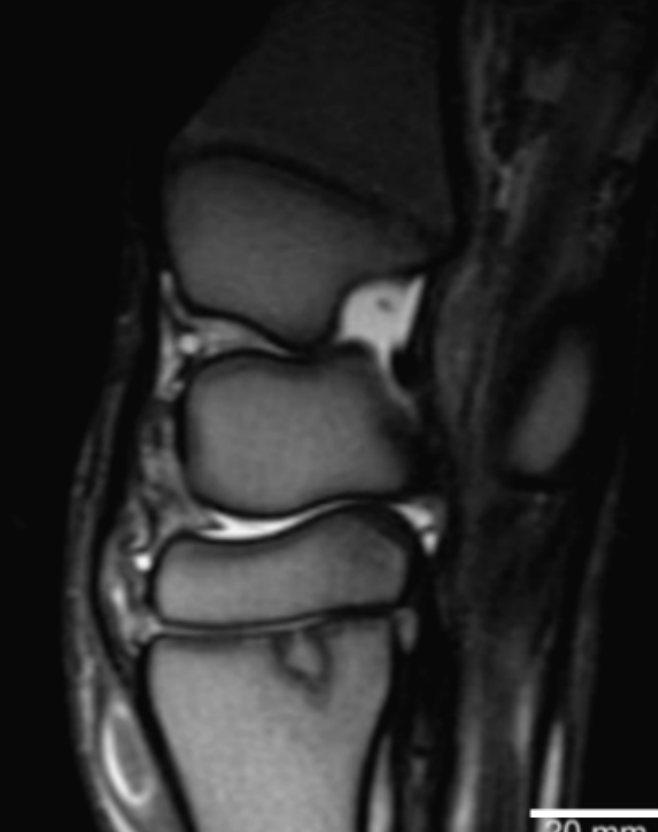

Name the labeled structures and determine the anomaly.

Intrahepatic PSS